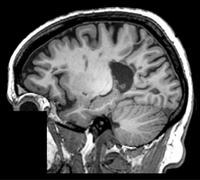

RegLib C01: MR Meningioma Align baseline MR of meningioma with follow-up.

brain tumor rigid+ affine MRI RegLib_C01.mrb